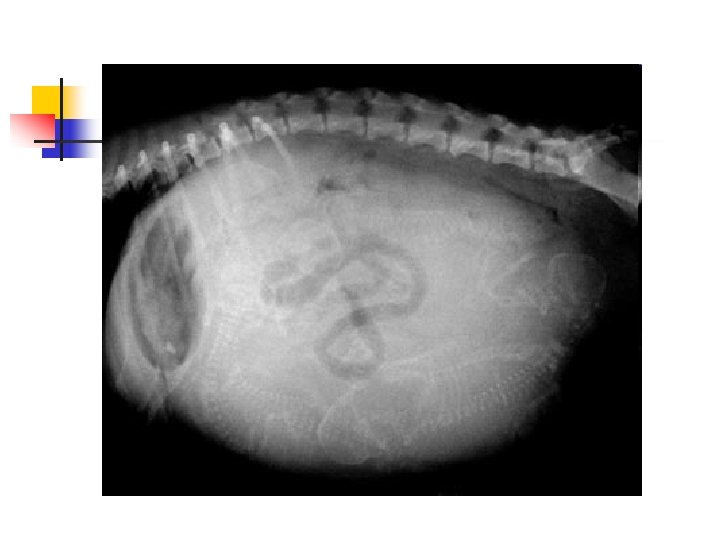

How Many Puppies? n n This dog's owner knew she was pregnant and was hoping for a big litter. Can you count how many puppies she is expecting? Here's a hint: the little puppy skeletons are visible. Try to count heads and backbones. It's harder than it looks because the puppies overlap each other!

Here is the answer: n n There are five puppies. I have outlined the heads and backbones in different colors to point them out.